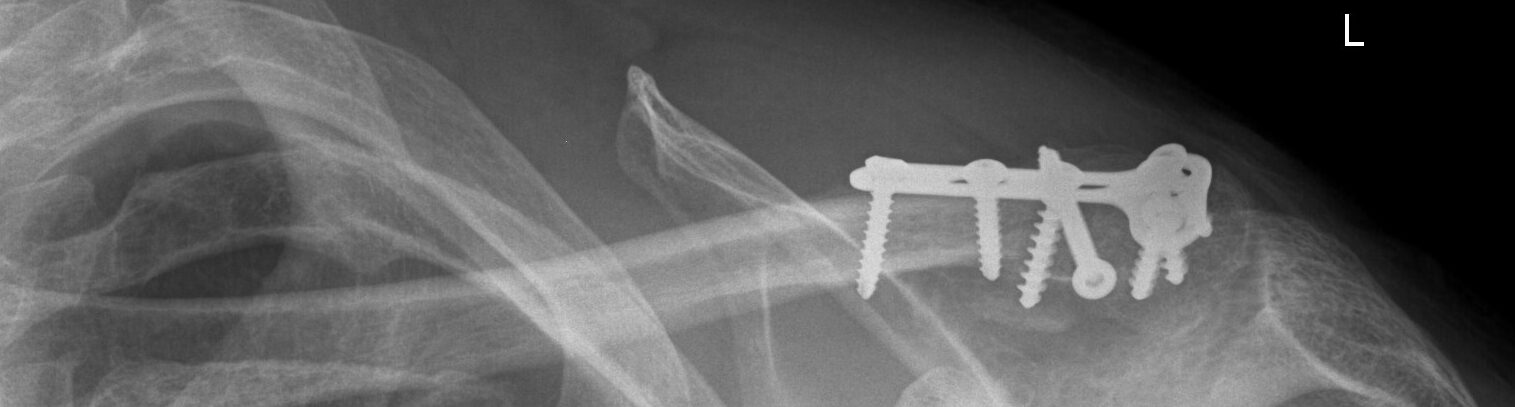

Schlüsselbeinbruch ist eine häufige Verletzung. Verschoben oder unverschoben ist essentiell für den weiteren Behandlungsverlauf.

Der Verletzungsgrad und die Art des Bruches entscheiden über eine konservative, arthroskopische oder offene operative Behandlung.